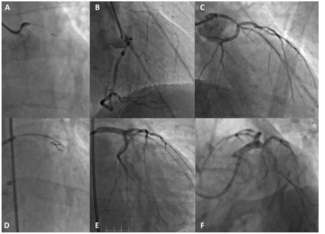

The authors report a rare case of simultaneous ST-segment elevation in the infero-lateral and anterior leads with acute double-coronaries thrombotic occlusion successfully treated with double primary percutaneous coronary intervention in a...